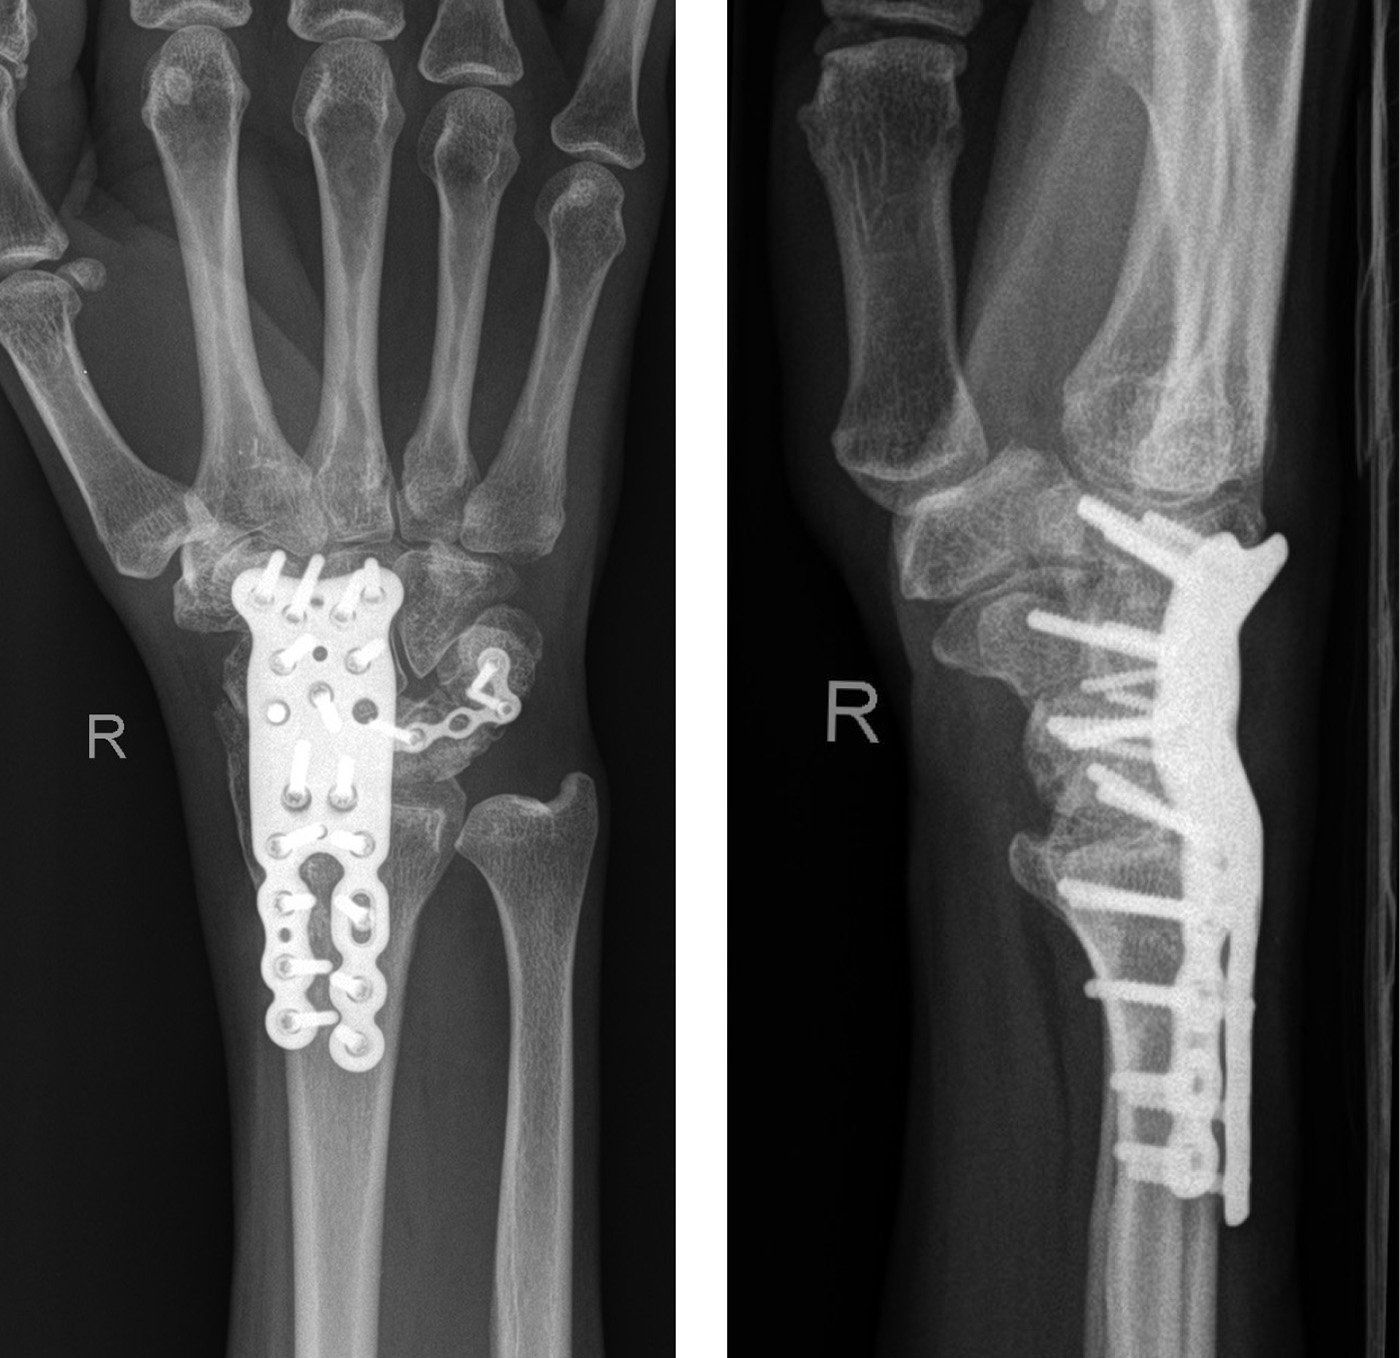

Nachteil dieser Methode ist jedoch die Entstehung einer Transferarthrose, d. h. eine Arthrose, die sich dann aufgrund der veränderten Kinematik auf das radioscaphoidale Gelenk erstreckt. Ein großes Problem stellten lange Zeit die Arthrosen des radiocarpalen Gelenkspaltes z. B. nach Radiusfrakturen dar. Die RSL-Fusion bietet hier einen Ausweg. Dabei werden das Kahnbein, das Mondbein und der Radius verblockt und es verbleibt eine Restbeweglichkeit im mediokarpalen Gelenkspalt. Der distale Kahnbeinpol sollte reseziert werden um das Bewegungsausmaß zu erweitern.

Speziell durch neue Implantate wurden die Möglichkeiten der Teilarthrodesen erweitert. Trotzdem sind die Voraussetzungen für die Arthrodesen zu beachten. Ausreichende Knochensubstanz und eine stabile Osteosynthese muss für die frühfunktionelle Nachbehandlung vorhanden sein. Bei den speziellen Platten ist insbesondere hier die Ringplatte bei der mediokarpalen Arthrodese zu erwähnen, wie sie von verschiedenen Herstellern angeboten werden

Natürlich müssen die Implantationstechniken, speziell der Ringplatte, beachtet werden, damit diese nicht dorsal anschlagen kann. Bei der radioscapholunären Teilarthrodese (RSL-Fusion) gab es in den letzten Jahren eine deutliche Verbesserung der Technik durch spezielle winkelstabile angepasste Platten, die eine frühsekundäre oder primäre Versorgung von extremen Trümmerfrakturen der Radiusgelenkfläche möglich machten, weiterhin ist diese bei einer nach operativer komplexer Radiusfraktur indiziert.